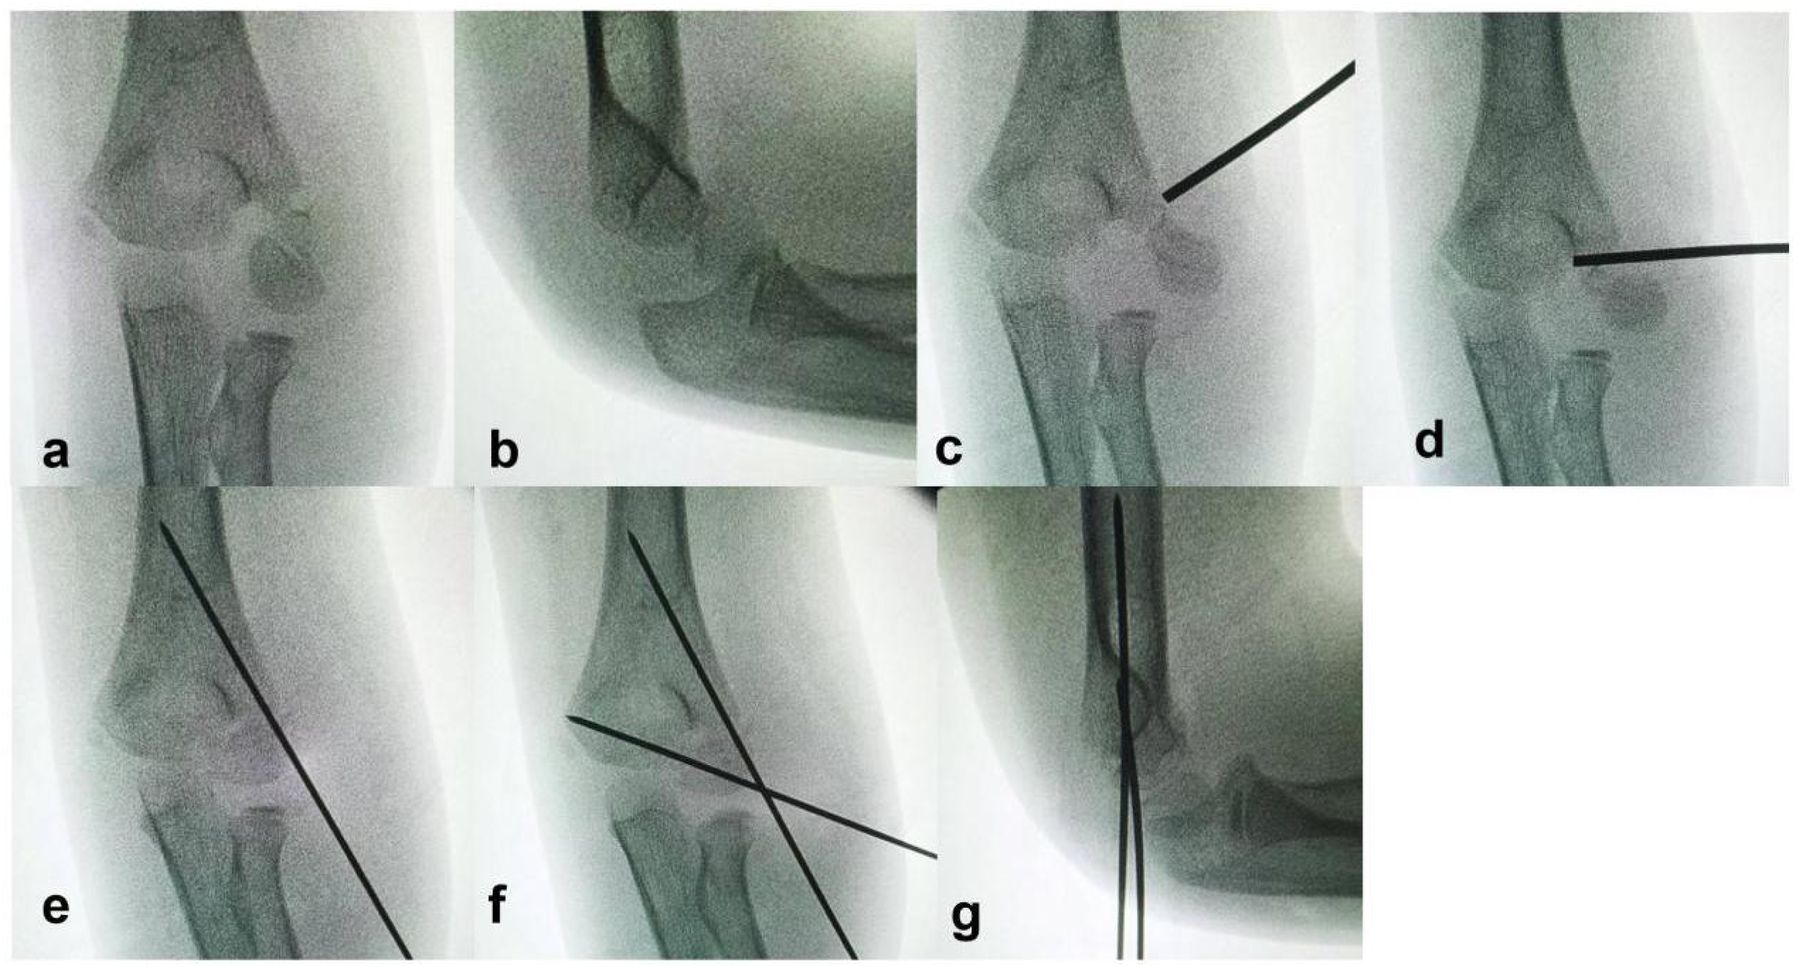

Closed Reduction Percutaneous Pinning (CRPP) (Figure 1): Under fluoroscopic guidance (C-arm), the position of the rotated fracture fragment was located. A 2.0 mm Kirschner wire was inserted at the medial edge of the rotated fragment. The wire tail was used as a lever to correct the rotational displacement, converting the Song V fracture to a Song IV or III pattern. Manual reduction was then performed to correct lateral displacement by applying compression along the fracture line. A 1.5 mm Kirschner wire was placed perpendicular to the fracture line for posterolateral fixation of the fragment. Further manual reduction was applied along the direction of the first K-wire until intraoperative fluoroscopy (AP, lateral, and oblique views) confirmed a fracture gap of less than 2 mm on all views, and a second 1.5 mm Kirschner wire was inserted for cross fixation. Both wires penetrated the opposite cortex.

Figure 1

Intraoperative fluoroscopic images of lever reduction and Kirschner wire fixation for a Song V lateral humeral condyle fracture. (a,b) Displaced fracture under fluoroscopy. (c) Kirschner wire tail placed between the rotated fragment and the proximal humeral metaphysis. (d) Lever reduction correcting the rotational displacement. (e) After manual correction of lateral displacement, one Kirschner wire fixes the fracture. (f,g) Compression along the first wire reduces the fracture gap, and the second wire is inserted.